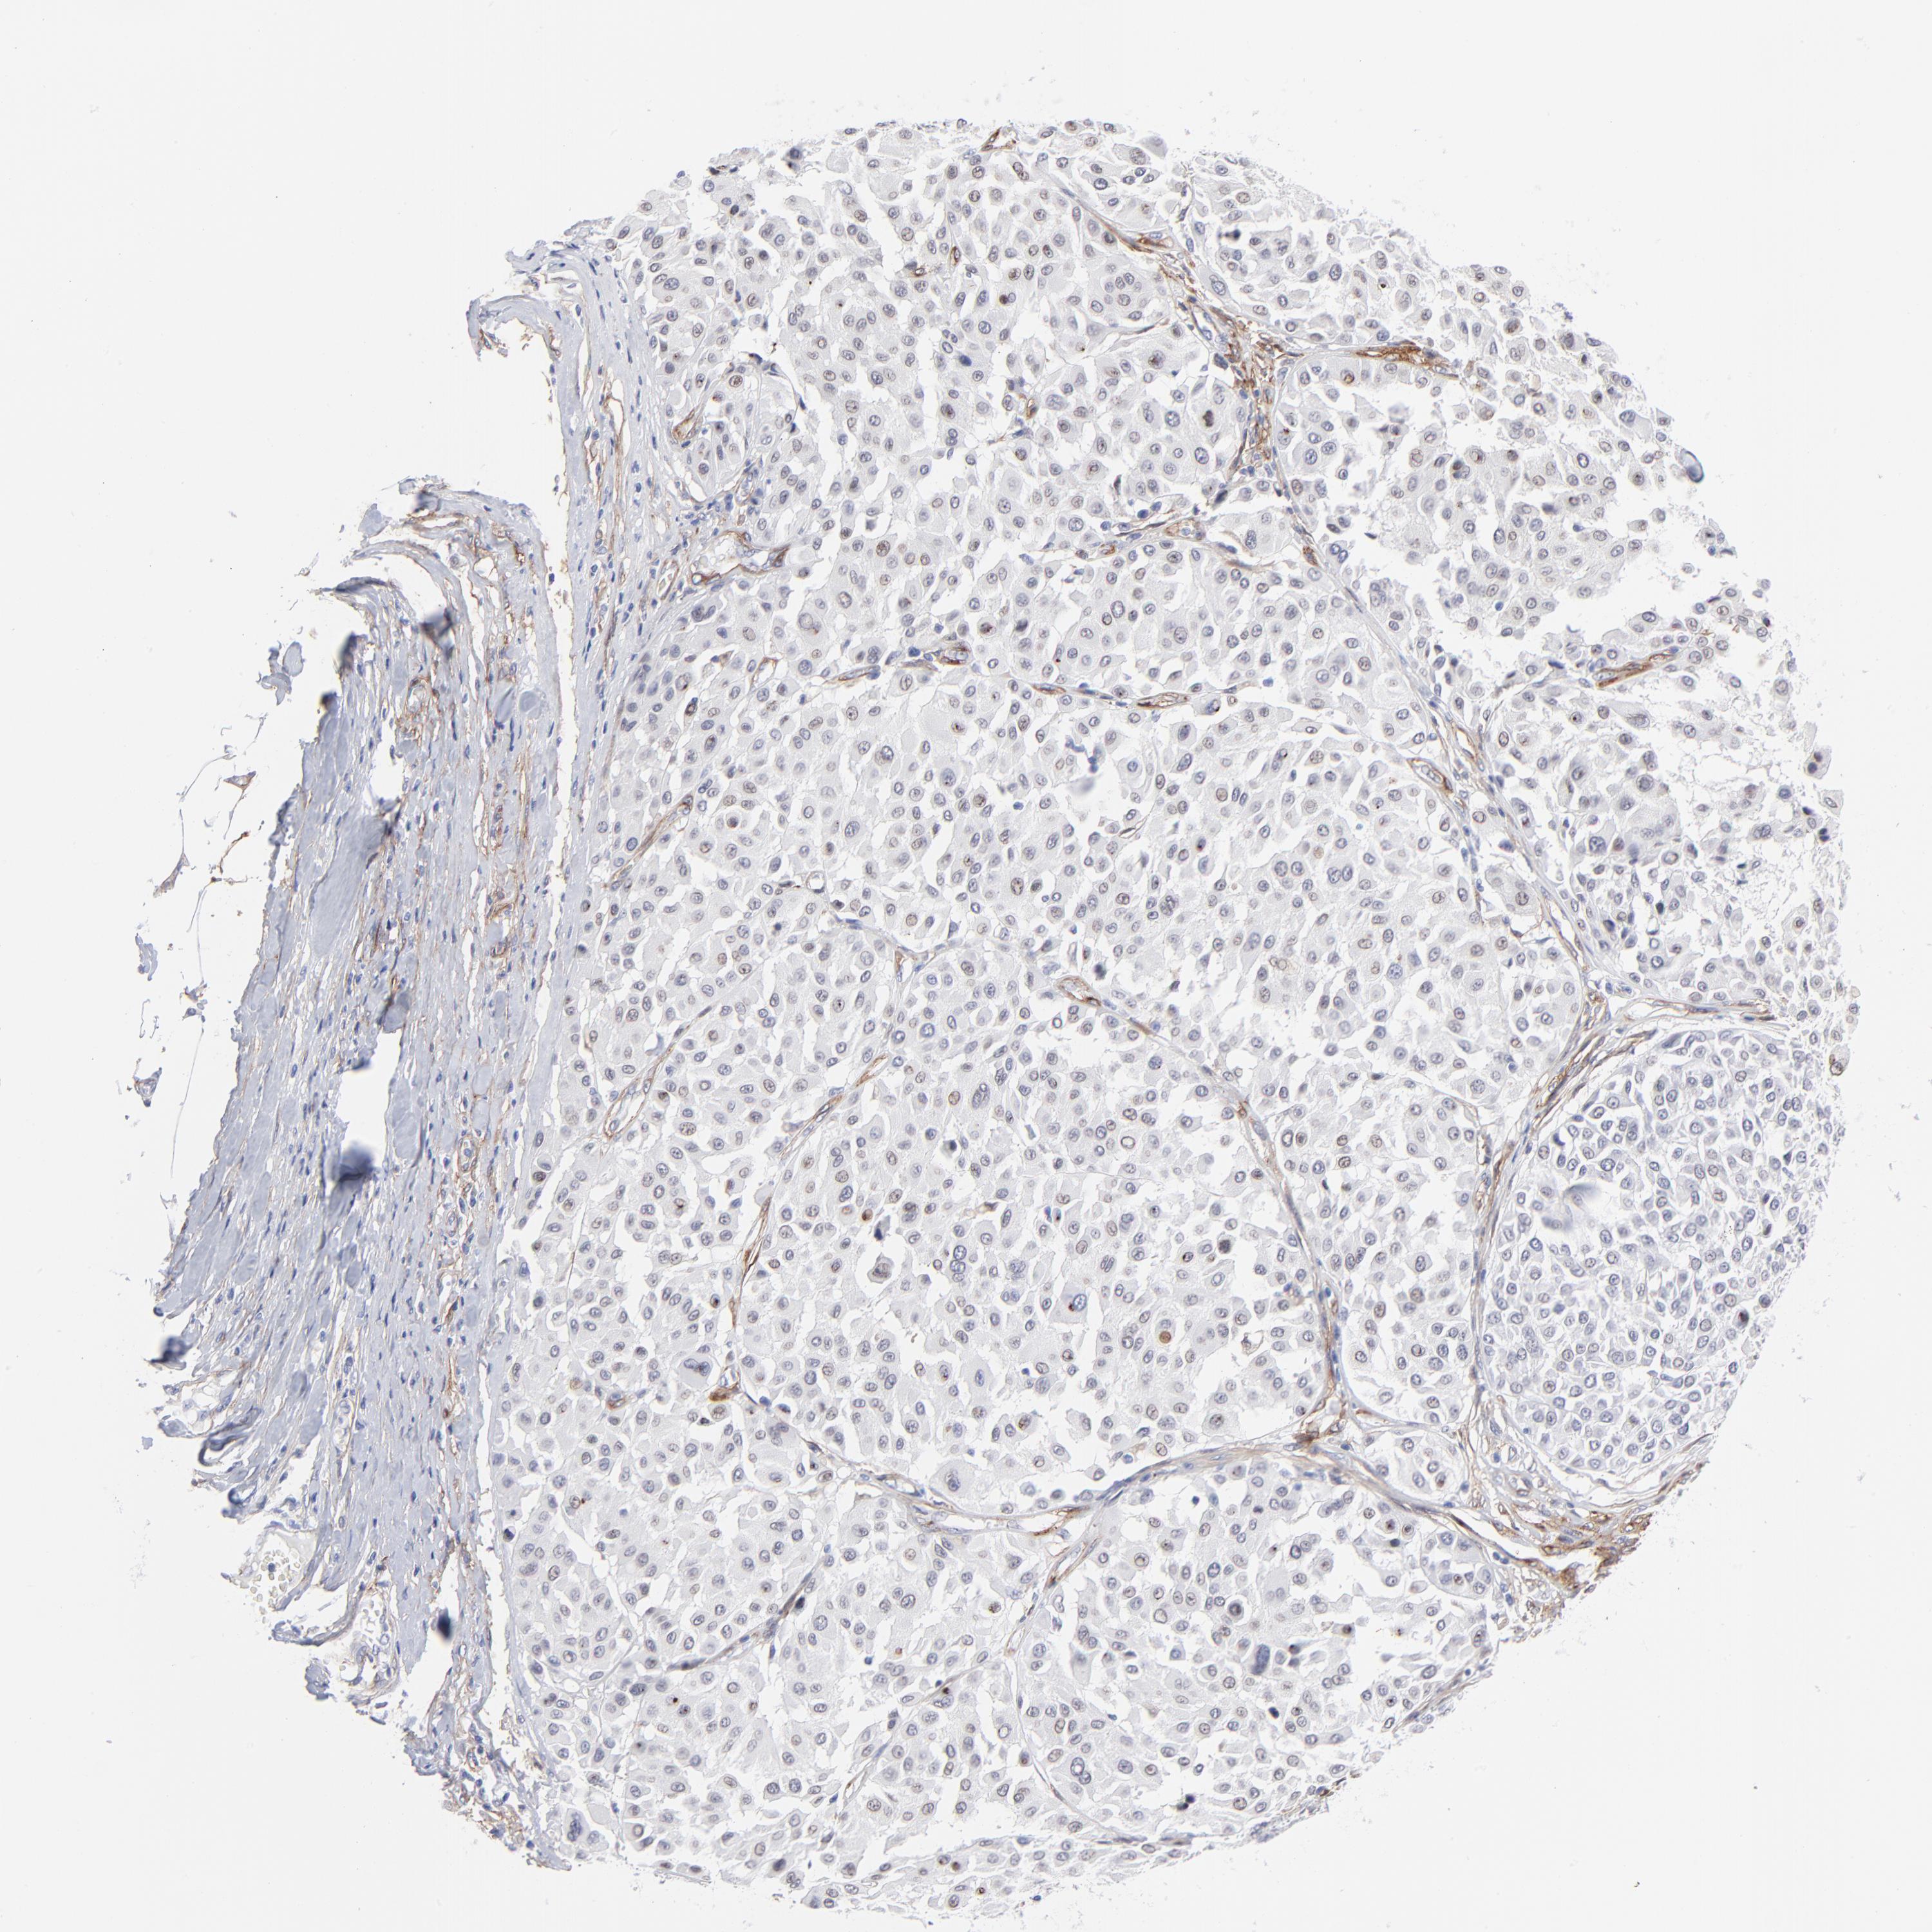

MELANOMA - Protein expressioni

A mouse-over function shows sample information and annotation data. Click on an image to view it in a full screen mode. Samples can be filtered based on level of antibody staining by selecting one or several of the following categories: high, medium, low and not detected. The assay and annotation is described here.

Note that samples used for immunohistochemistry by the Human Protein Atlas do not correspond to samples in the TCGA dataset.

Antibody stainingi

Antibody staining in the annotated cell types in the current human tissue is reported as not detected, low, medium, or high, based on conventional immunohistochemistry profiling in selected tissues. This score is based on the combination of the staining intensity and fraction of stained cells.

Each image is clickable and will lead to virtual microscopy that enables deeper exploration of all samples and also displays staining intensity scores, fraction scores and subcellular localization as well as patient and tissue information for each sample.

Antibody CAB003842

Antibody CAB018144

Staining

High

Medium

Low

Not detected

Intensity

Strong

Moderate

Weak

Negative

Quantity

>75%

75%-25%

<25%

None

Location

Nuclear

Cytoplasmic/membranous

Cytoplasmic/membranous,nuclear

Malignant melanoma, NOS

Malignant melanoma, Metastatic site